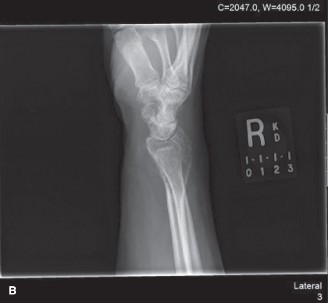

Initial diagnostic workup commenced with plain radiographs of the right knee, followed by advanced cross-sectional imaging to define the local extent of the disease and plan potential surgical intervention.

Anteroposterior and lateral radiographs of the right knee demonstrated an eccentric, purely lytic lesion in the metadiaphyseal region of the distal femur, extending into the subchondral bone of the lateral femoral condyle. The lesion was expansile, with a narrow zone of transition, and showed no significant sclerotic rim, a classic radiographic hallmark of an active benign or low-grade malignant bone tumor. Cortical thinning and a pathological stress fracture line were noted along the lateral cortex. There was no evidence of periosteal reaction, Codman triangle, or internal matrix mineralization (no chondroid rings/arcs or osteoid cloudiness). The epiphyseal plate was noted to be completely fused, consistent with the patient's skeletal maturity.

Figure 1: Initial AP radiograph demonstrating an expansile lytic lesion in the distal femur, extending to the subchondral bone, with cortical thinning and lack of sclerotic margin.